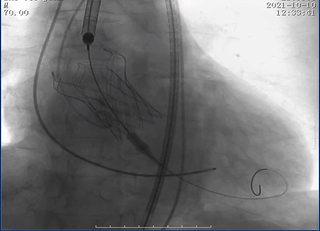

瓣膜释放至可回收极限处造影

瓣膜完全释放后造影

在多学科协作下,高州市人民医院心脏外科陈凯明、刘浪教授团队完成首例VitaFlow Liberty™主动脉瓣置换。经过2个小时紧张有序的操作,术中借助VitaFlow Liberty™的可回收技术,帮助瓣膜精准定位植入,术后造影检查和心脏彩超评估瓣膜形态活动良好,没有瓣周漏。手术取得圆满成功,患者心功能改善显著,次日转回普通病房。